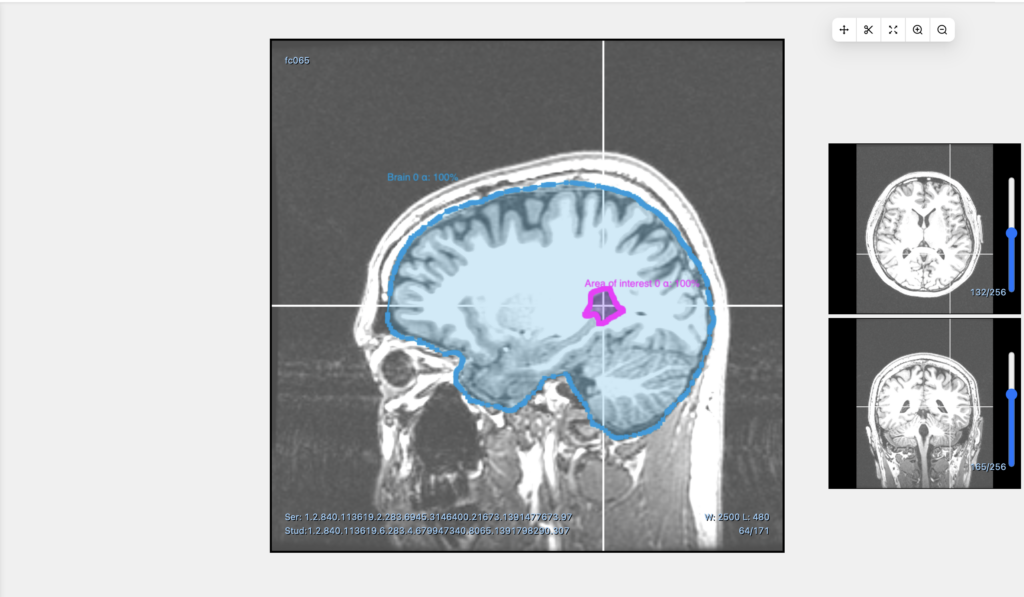

Medtech platform Optellum secures $14m Series A to use AI to treat early-stage lung cancer

As artificial intelligence (AI) continues to grow more sophisticated, the possibilities of its usage continue to expand. From creating original …